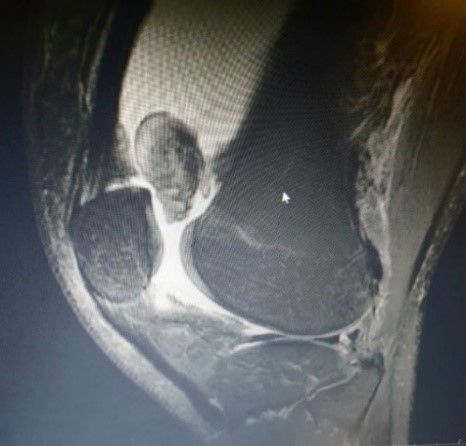

Μαγνητική Τομογραφία.

Η MRI είναι η απεικονιστική μέθοδος εκλογής. Σε εντοπισμένη ΛΥ θα δείξει μια οζώδη μάζα. Στη διάχυτο ΛΥ θα εμφανίσει εκτεταμένη πάχυνση της επένδυσης της άρθρωσης ή εκτεταμένη μάζα, πιθανώς με καταστροφικές διαβρώσεις του χόνδρου και κύστεις στα οστά. Χαρακτηριστικά δείχνει περιοχές σήματος χαμηλής έντασης (οφειλόμενου στις παραμαγνητικές δράσεις της αιμοσιδηρίνης και στον ινώδη ιστό), σε συνδυασμό με περιοχές σήματος υψηλής έντασης(οφειλόμενου στο οιδηματώδη και παχύ υμένα και το περιεχόμενο λίπος).